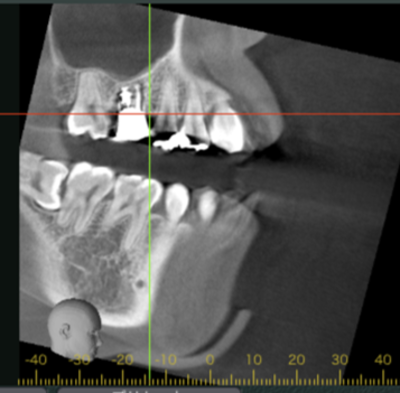

移植12ヶ月後のCT画像①

移植12ヶ月後のCT画像②

移植12ヶ月後。CT画像では、歯根周囲に骨が形成されていることが確認できる。

患者さまは特に違和感なく快適に過ごされているとのこと。